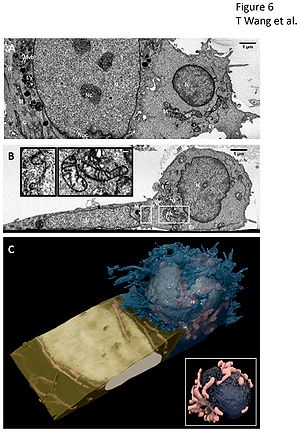

- 4.13 Three-Dimensional Imaging of HIV-1 Virological Synapses Reveals Membrane Architectures Involved in Virus Transmission